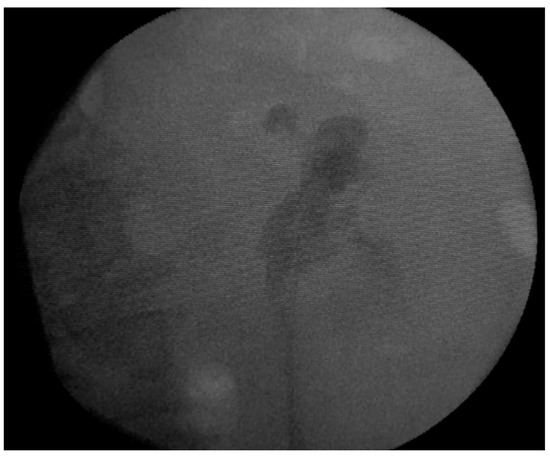

Following the retrograde ureteropyelography, we inserted a left double-J ureteric stent, with the intention of facilitating the urinary drainage from the left kidney, considering that the opposite right kidney was hypoplastic (Figure 3).

Figure 3. Fluoroscopic image after the placement of the left ureteric stent.